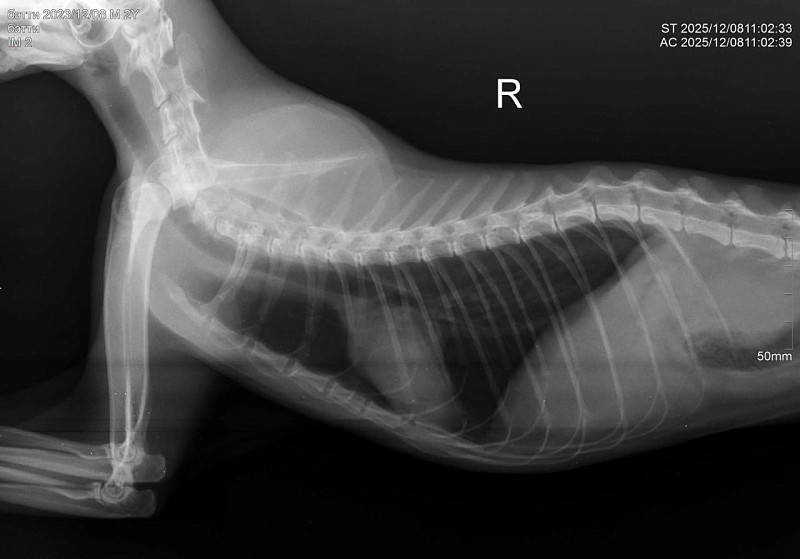

Здравствуйте! У нас кошка 10 дней находилась на улице. Через 10 дней вернулась никакая, сильное истощение, дезориентация. Кошка ходит и стукаетсях, как будто потеря в пространстве. Самостоятельно питаться не может. Повезли в ветеринарке, сделали рентген, говорят возможно ЧМТ или оттек головного мозга. Выписали препараты. Кормим со шприца, сейчас уже чуть бодрее стала, дней пять прошло после визита в ветеринару. Аппетит хороший. Но самостоятельно есть не может, зрительный рефлекс слабый. Глазки чистые.